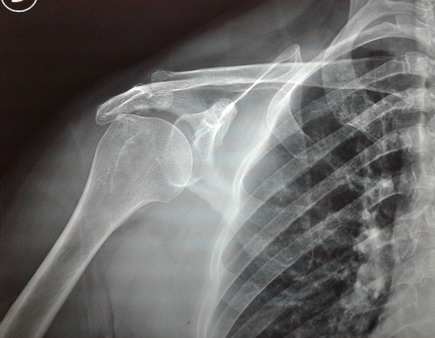

Idx: Ruptura de tendón supraespinoso derecho

-Radiografía McNab y su utilidad en lesiones manguito rotador

-Mecanismo muscular en ruptura del manguito rotador y clasificaciones

-Anatomía y técnicas de reparación Artroscópica de manguito rotador